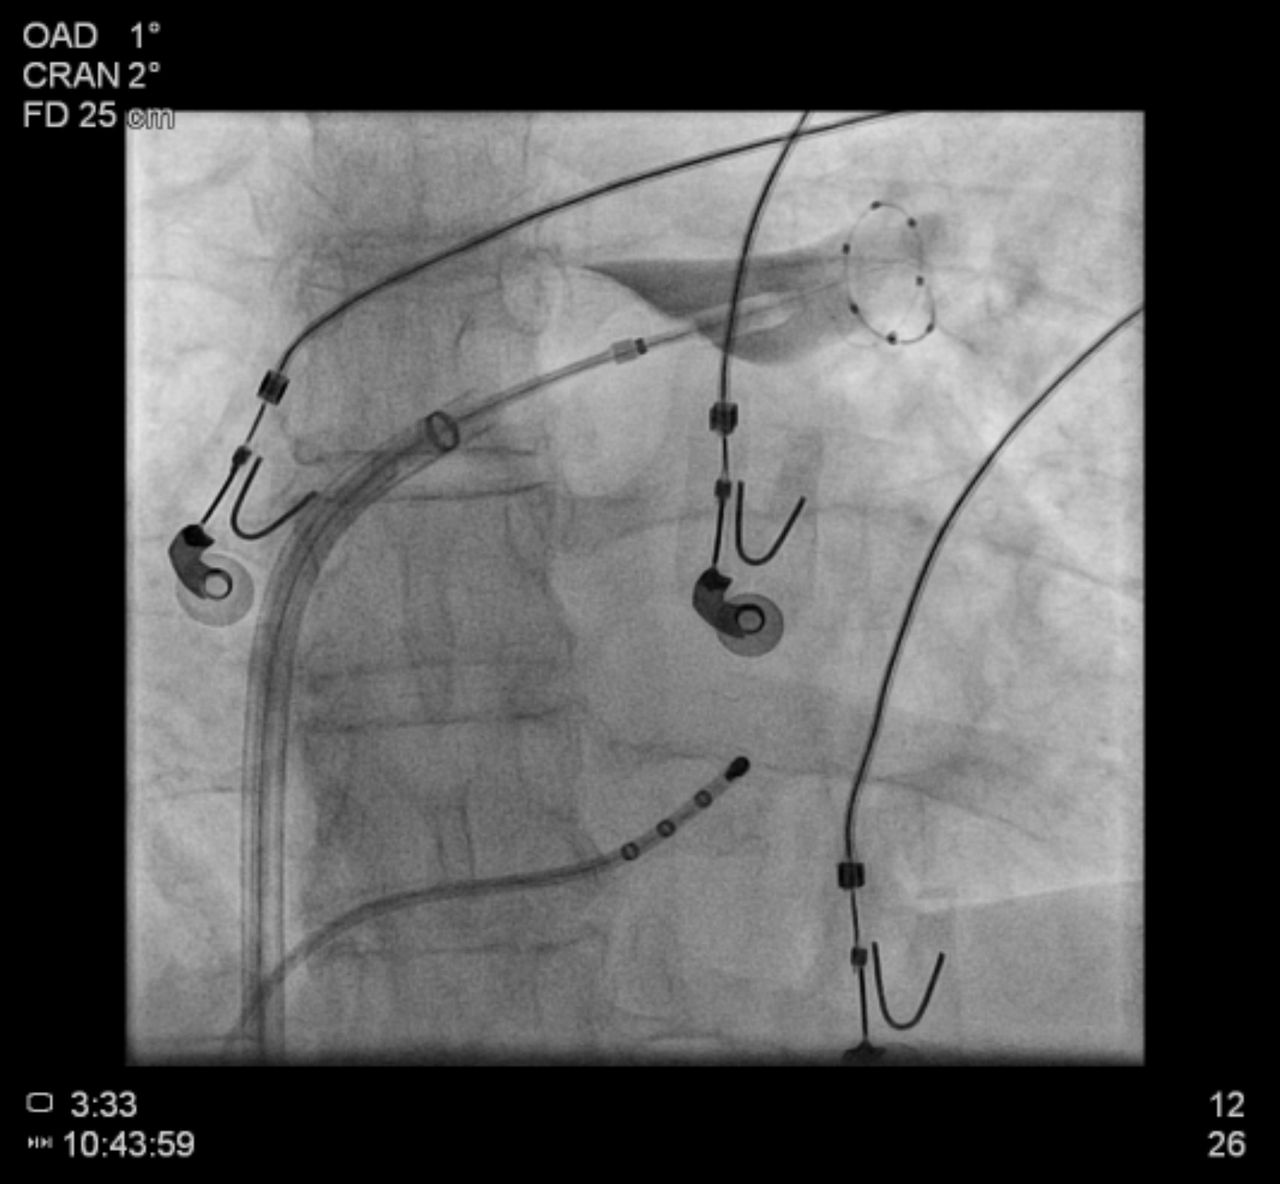

El Dr. Ernesto Díaz Infante (Sevilla, 1973) es un cardiólogo español reconocido en el campo de las arritmias cardiacas, muerte súbita y manejo de dispositivos de estimulación cardiacos (marcapasos, desfibriladores y resincronizadores cardiacos). Tiene una amplia experiencia en la ablación con cáteter de las arritmias más complejas, tanto fibrilación auricular, como taquicardia ventricular a nivel endo y epicárdico y arritmias en pacientes con cardiopatías congénitas complejas. Actualmente es el Director de la Unidad de Arritmias y Estimulación Cardiaca del Hospital Universitario Virgen Macarena de Sevilla, Profesor Asociado de Medicina en Sevilla y en la medicina privada es el Director de la Unidad de Arritmias del Hospital Vithas Nisa Sevilla.